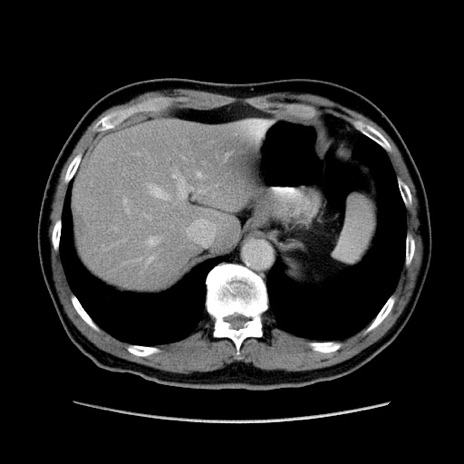

症例34(横断像)

【症例】60歳代 男性

【主訴】右鼠径部膨隆

【現病歴】1年程前より右鼠径部膨隆あり。自己にて還納可能だったため放置していた。3時間前より右鼠径部の脱出を認め、還納困難となり受診。

【身体所見】右鼠径部に小児頭大の膨隆あり。弾性硬であり、用手還納は困難。左鼠径部にも膨隆を認める。脱出はなし。

【データ】WBC 15500、CRP 測定なし